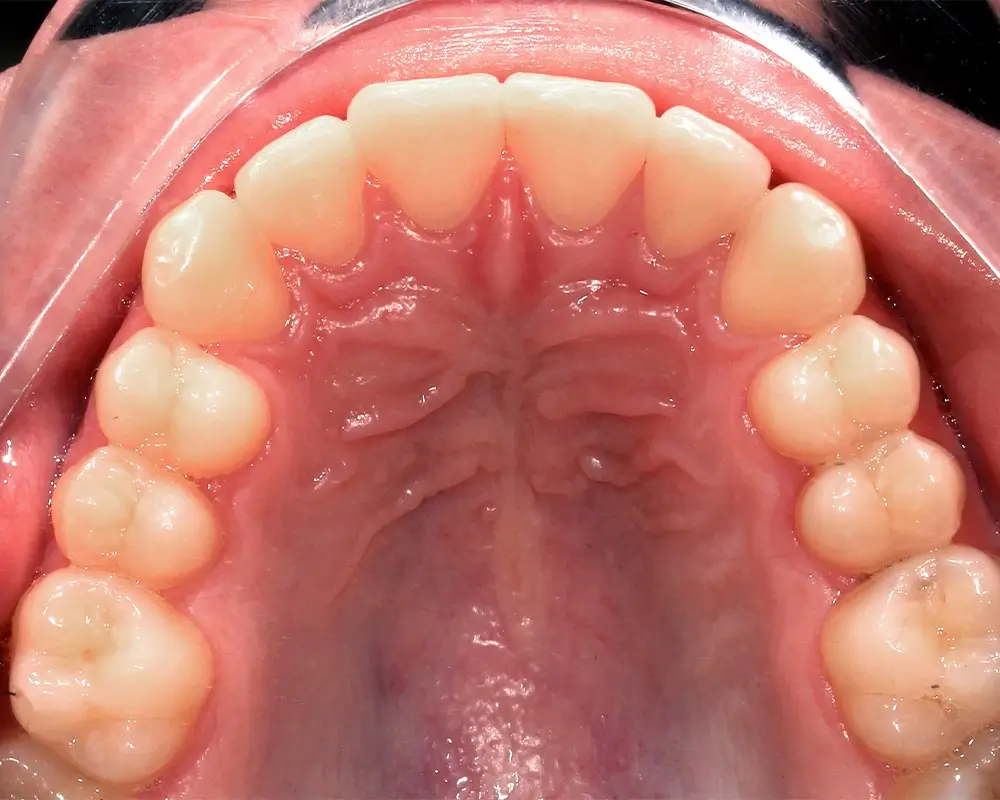

Скученность - Кейс 25

Эффективность устранения дефекта прикуса посредством элайнеров FlexiLigner.

16

Количество кап НЧ

Результаты лечения